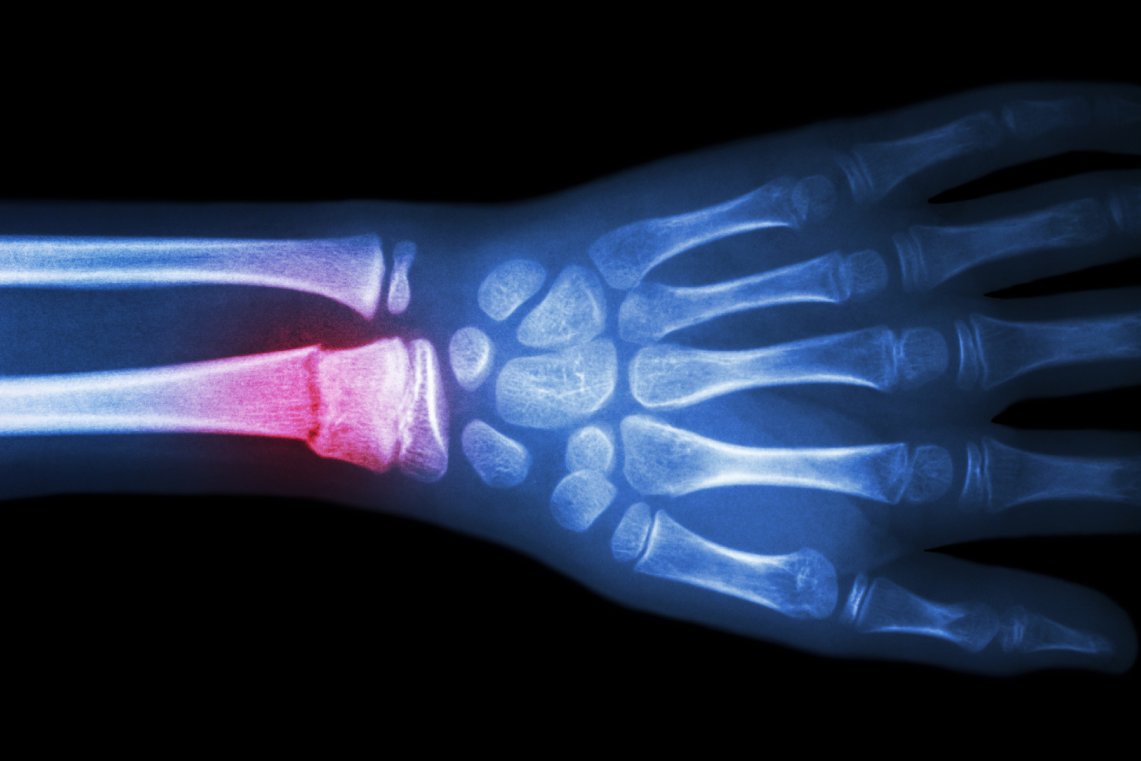

مرحله ترمیم سخت با معدنیسازی کالوس رخ میدهد. استئوبلاستها کلسیم و فسفات را رسوب میدهند و استخوان اسفنجی (trabecular) تشکیل میشود، سپس به استخوان کورتیکال (سخت) تبدیل میگردد. این فاز ۳-۱۲ هفته طول میکشد و در رادیوگرافی، سایه کالوس قابل مشاهده است. شواهد از AAOS تأیید میکند که استخوان ترمیمشده اغلب متراکمتر و قویتر از قبل است، زیرا کالوس اضافی استحکام بیشتری فراهم میکند. با این وجود، در افراد مسن یا بیماران دیابتی، معدنیسازی ناقص شایع است و ممکن است به جوشنخوردن منجر شود، که در ۵-۱۰ درصد موارد رخ میدهد.